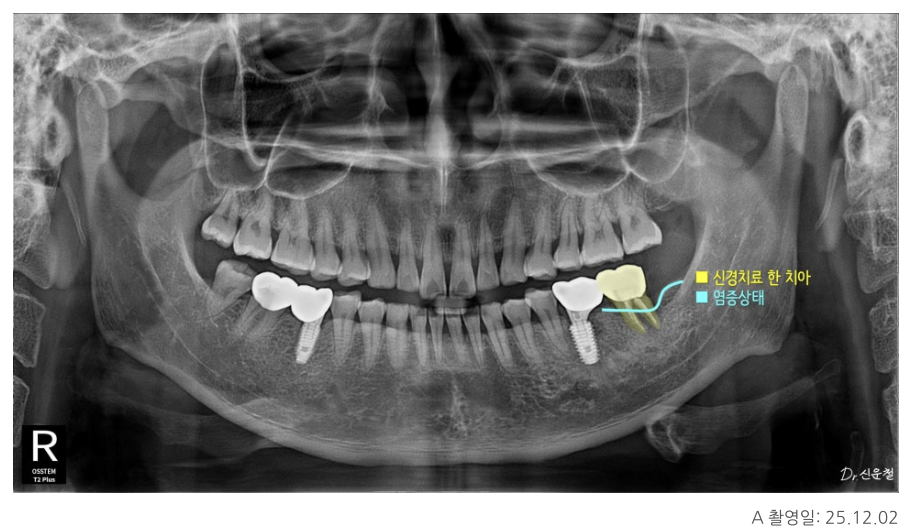

실제 내원 사례 중에는

이미 신경치료를 받은 어금니에서

잇몸이 다시 붓고 고름이 차

발치 진단을 받고 오신 분도 계셨습니다.

또 다른 분은

“신경치료가 어렵다”는 설명을 듣고

의뢰로 내원하신 경우였습니다.

이 치아의 특징은 치아 안쪽 신경이 지나가는 길이

오랜 시간에 걸쳐 점점 막혀 있던 상태,

즉 석회화였습니다.